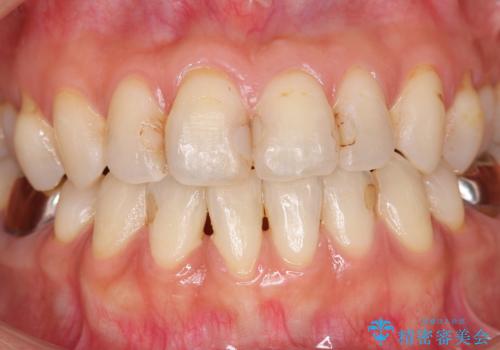

前歯の劣化したコンポジットレジン修復をセラミッククラウンへ

- 数年前に前歯の虫歯治療し、コンポジットレジン修復がなされてい箇所の審美障害の改善を希望され来院されました。

再度レジン修復を行うか、劣化のスピードは遅いが歯の削合が必要なセラミッククラウンの治療の選択肢をご提案し、今後のやりかえの心配の少ないセラミッククラウン治療を希望されました。

- 52.8万円(ジルコニアクラウン×4・仮歯×4)費用は治療当時の料金となります